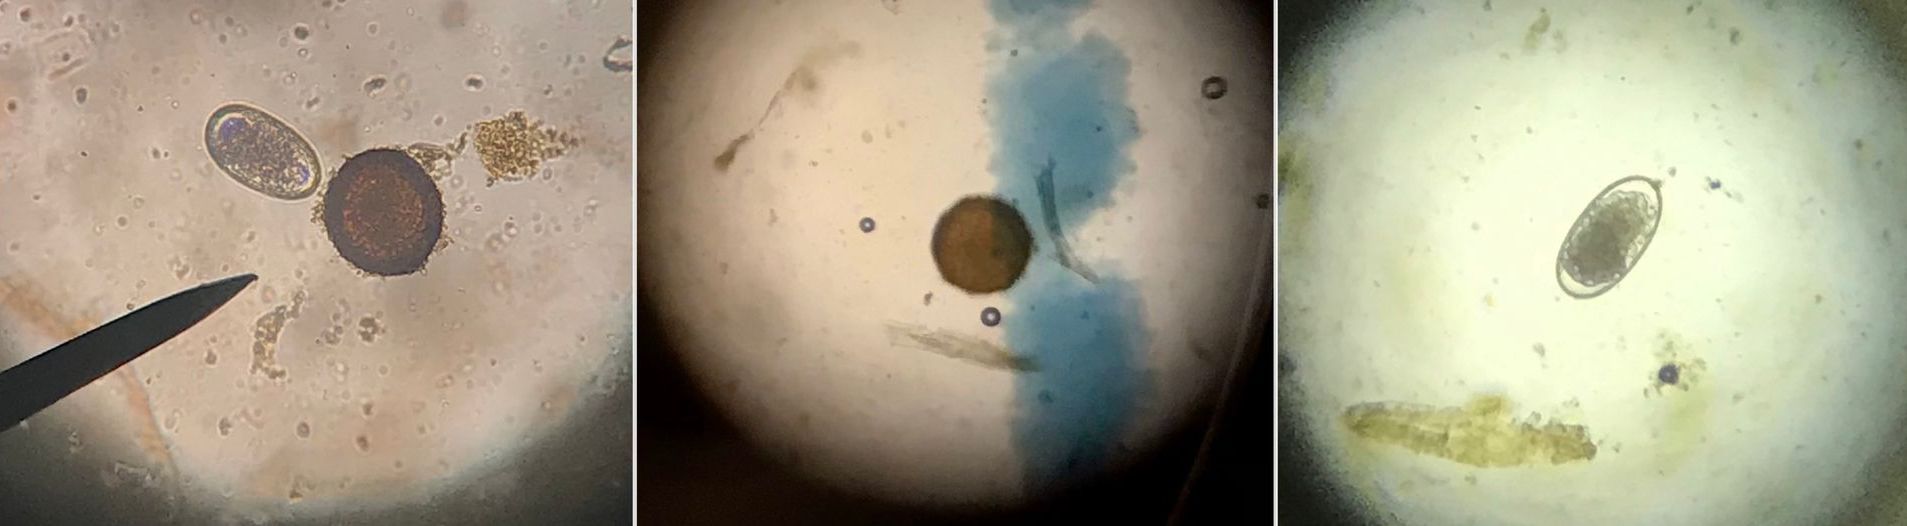

Om verdere ontwikkeling van resistentie zoveel mogelijk te vertragen is het van groot belang dat er zorgvuldig wordt omgegaan met het gebruiken van de beschikbare wormmiddelen. Mestonderzoek is hierbij de belangrijkste tool. Mestonderzoek laat je doen om inzicht te krijgen in de mate van wormbesmetting bij het paard (of ieder ander dier). Met een mengsel van een kleine hoeveelheid mest in een zout- of suikeroplossing kunnen we onder de microscoop kijken of en zo ja, hoeveel wormeieren er aanwezig zijn en van welke wormsoort deze afkomstig zijn. Middels een berekening wordt het EPG (eieren per gram) bepaald. De hoogte van het EPG bepaalt of het nodig is om het paard te ontwormen. Bij de afweging om wel of niet te ontwormen wordt ook gekeken naar zaken zoals leeftijd, besmettingsdruk en eventueel andere specifieke omstandigheden.

De wormen die de meeste problemen geven bij paarden zijn de kleine strongyliden (kleine rode bloedworm) en de spoelworm. Kleine strongyliden komen voor bij paarden van alle leeftijden maar zijn het meest gevaarlijk voor dieren in de leeftijd van 1 tot 3 jaar. Spoelwormen zijn vooral gevaarlijk voor veulens en jaarlingen, maar komen soms ook bij volwassen paarden voor.